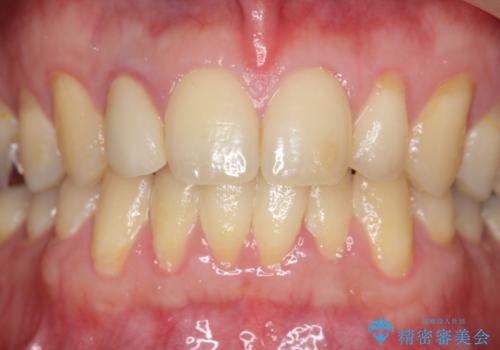

- 金属を使っていない被せ物に替えたいといらっしゃった方の症例です。

再根管治療終了後、オールセラミッククラウンによる補綴を行いました。

今回用いたオールセラミッククラウンはジルコニアフレームという白い素材の上にセラミックを盛っているため、審美性が非常に高いのが特徴です。

また、ジルコニアは人工ダイヤモンドの材料にも使われているほど高い強度を持っており、そのためオールセラミッククラウンは審美性だけでなく、奥歯やブリッジの補綴も可能とするクラウンです。